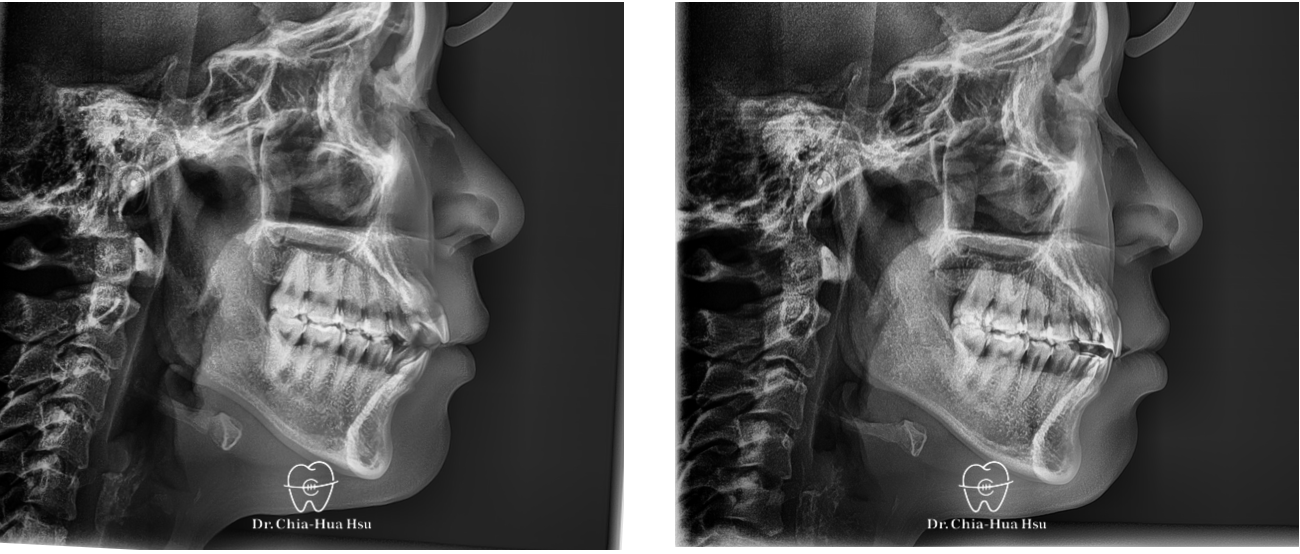

• 問題分析:患者是骨骼一類咬合(Skeletal Class I)合併前牙開咬。

• 治療方式:使用自鎖式金屬矯正器,配合齒間鄰接面修磨,再搭配齒間橡皮筋的使用,使開咬順利解決。另外,也有教導患者正確的舌頭擺放位置與運動練習。

• 治療時間:9個月。

• 治療結果:咬合恢復正常,微笑曲線更自然!

治療前

治療後